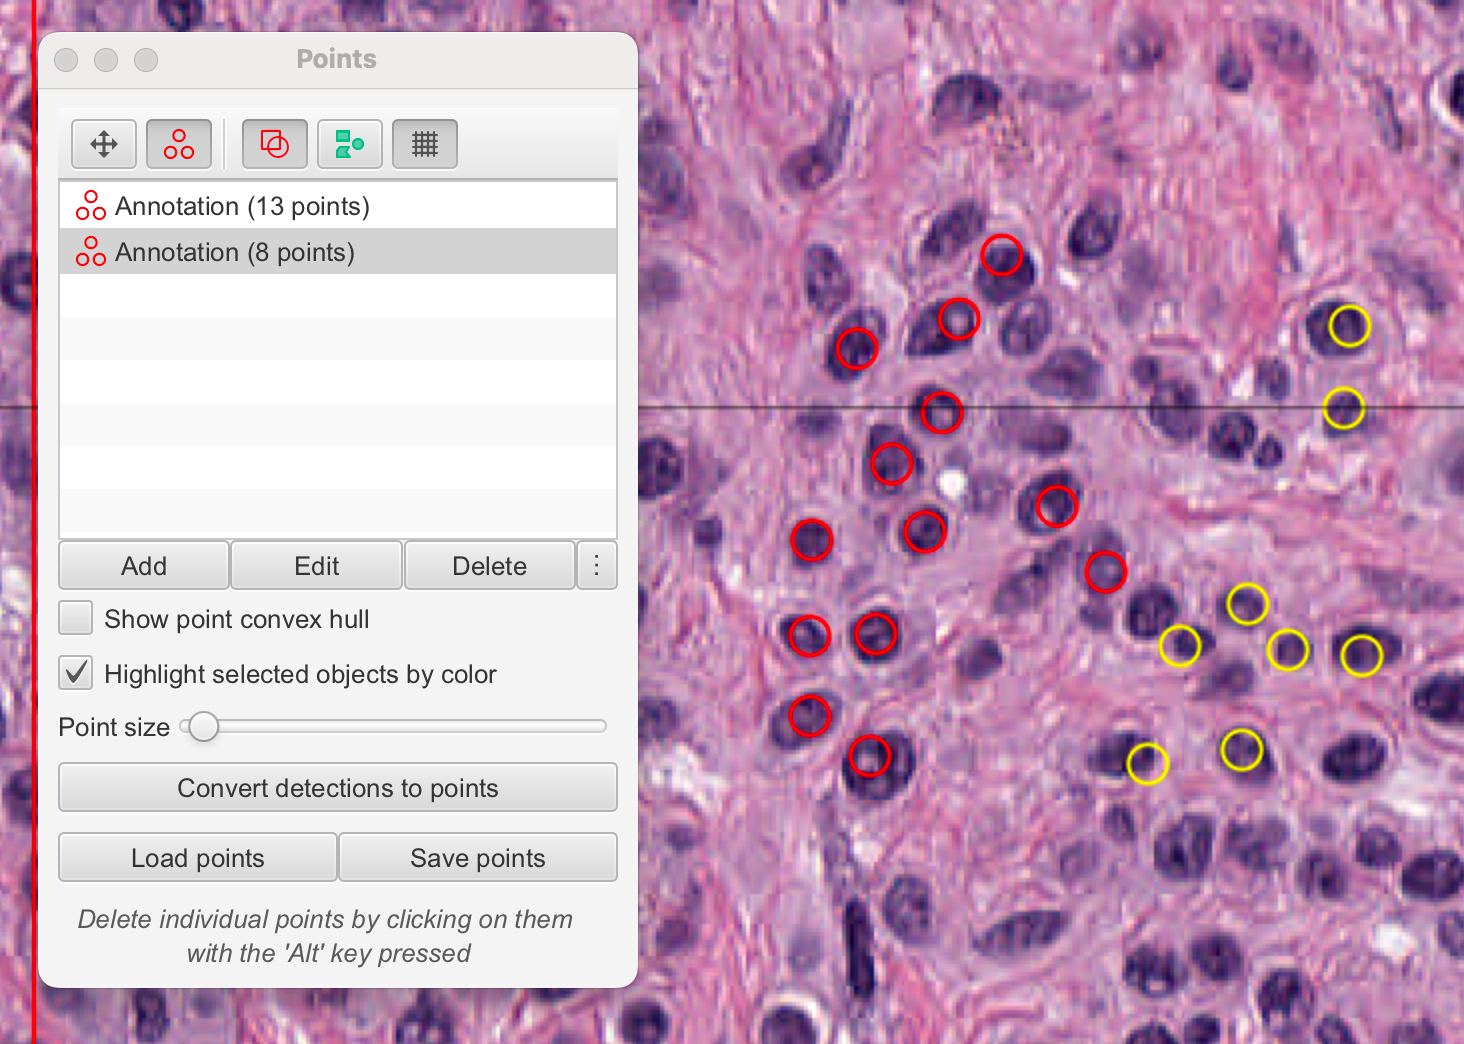

四、手动计数

计数是病理学和生物图像分析中的常见任务。

本节描述了如何使用QuPath手动计数不同类型的细胞——在这里,阳性(棕色)和阴性(蓝色)肿瘤细胞经过Ki67染色。

4-2:点击细胞

为了开始认真计数,请在工具栏中选择点工具Point tool。这将自动打开一个计数面板,其中包含一个单独的点注释列表。然后,您可以在图像上开始点击,每次点击都会创建一个点。

在此阶段,您应该只点击同一类细胞(例如阳性细胞)。

在您点击了一段时间后,您可能希望开始计数另一类细胞(例如“阴性”)。在计数面板中按添加按钮将开始一个新的注释来收集您的新点集,但您可能希望更清楚地区分点。

您可以通过双击计数面板中的条目,并设置更详细的名字和颜色来实现这一点。无论何时在图像上点击,您都会向列表中选定的条目添加点。